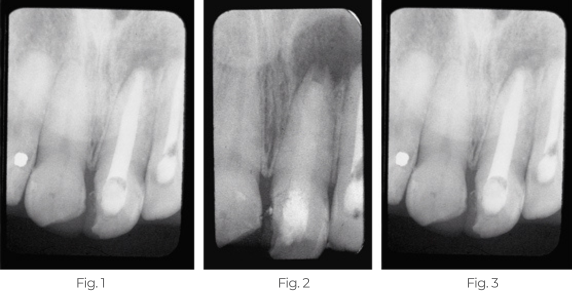

Behandlung einer persistierenden periapikalen Läsion

Der Patient war seit 4 Jahren wegen einer persistierenden periapikalen Läsion mit ständiger Drainage seines linken zentralen Schneidezahns in Behandlung. Eine retrograde Operation zur Entfernung der Zyste war geplant. Als vorübergehende Maßnahme vor der Operation wurde die Pulpa entfernt und TempCanal in den Kanal eingesetzt. Der obere linke seitliche Schneidezahn war ebenfalls nicht vital und wurde bei demselben Termin endodontisch behandelt und mit Pulpdent® Root Canal Sealer obturiert.

Abb. 1: Die Röntgenaufnahme zeigt eine periapikale Läsion, die die oberen linken mittleren und seitlichen Schneidezähne betrifft.

Abb. 2: Sechs Wochen nach dem Einsetzen von TempCanal zeigt die Röntgenaufnahme eine Trabekulierung im periapikalen Bereich. Der chirurgische Eingriff wurde verschoben, der TempCanal-Verband wurde gewechselt und der Fall wurde bis zur Abheilung der periapikalen Läsion weiterverfolgt.

Abb. 3: Die Nachuntersuchung nach einem Jahr zeigt die Abheilung ohne chirurgischen Eingriff und die endgültige Obturation mit Pulpdent® Root Canal Sealer unter Verwendung der Pressure Syringe-Technik.